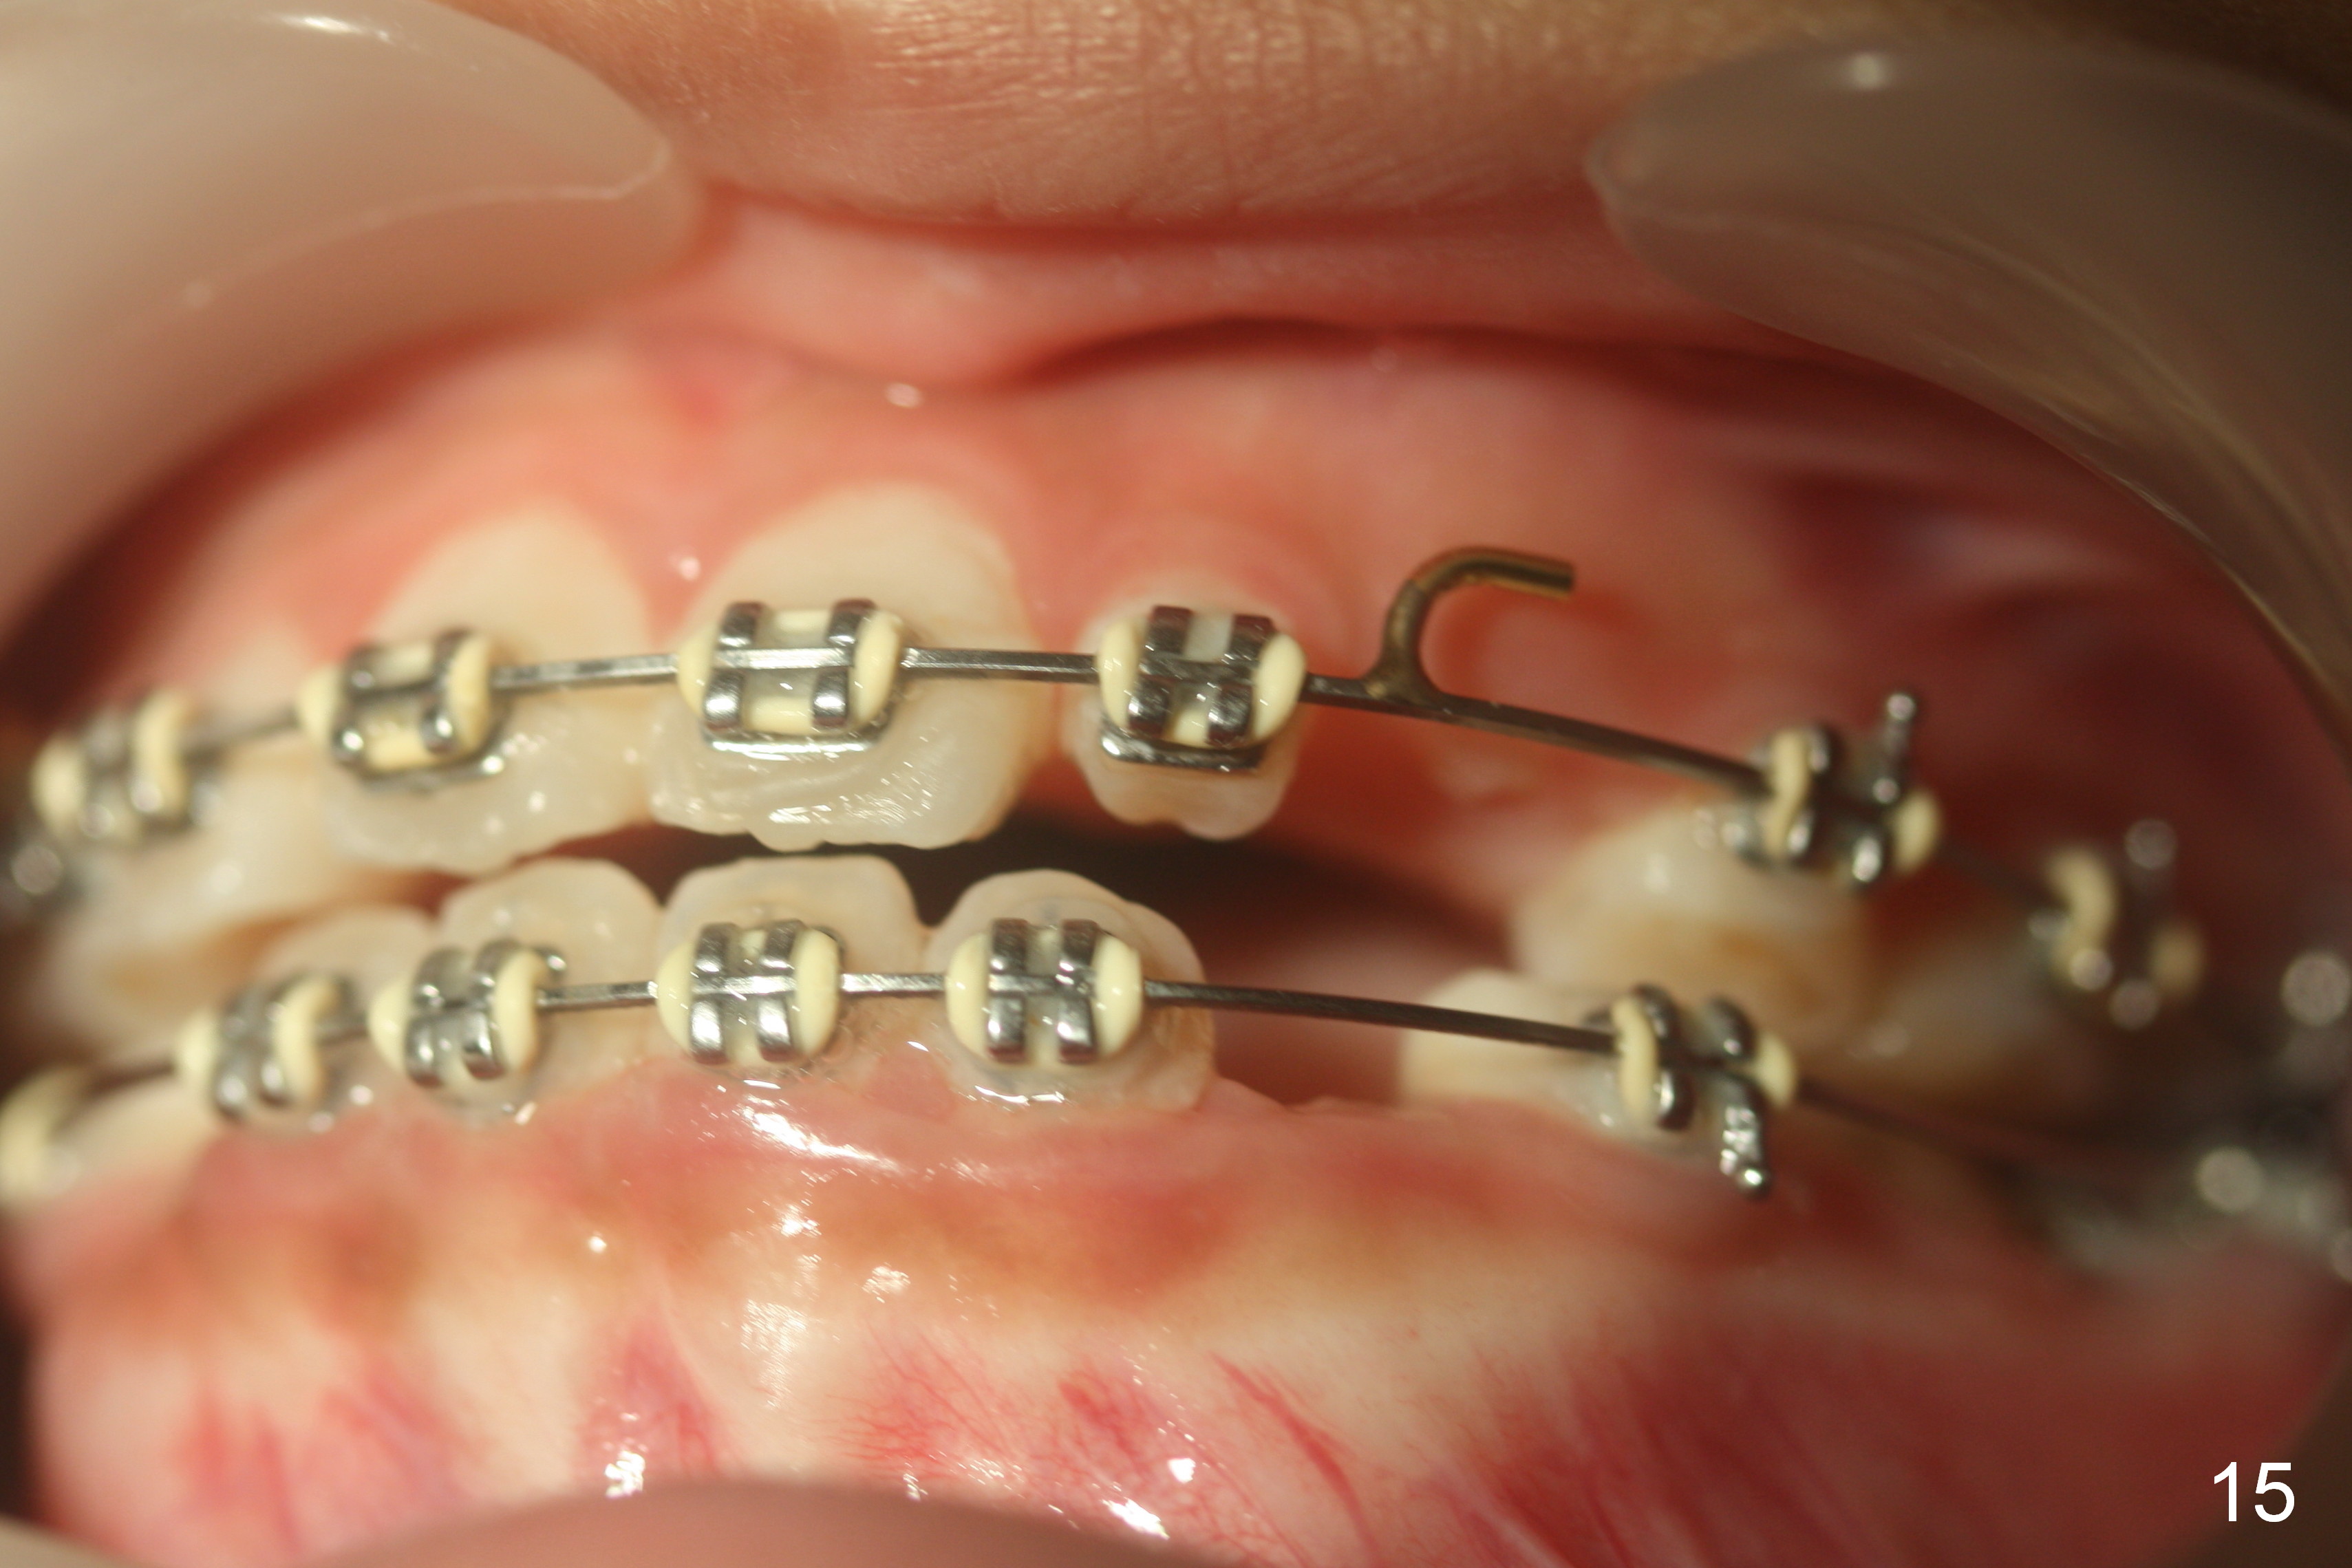

Between the 2nd and 3rd months, the patient is instructed to wear face bow after school. Overjet is WNL. Then the kit wears face bow before sleep. Fig.12-15 are taken 4 months of face bow. Can we ask the girl to wear it every night for 2 weeks and then every other night for another 2 weeks before removing brackets?